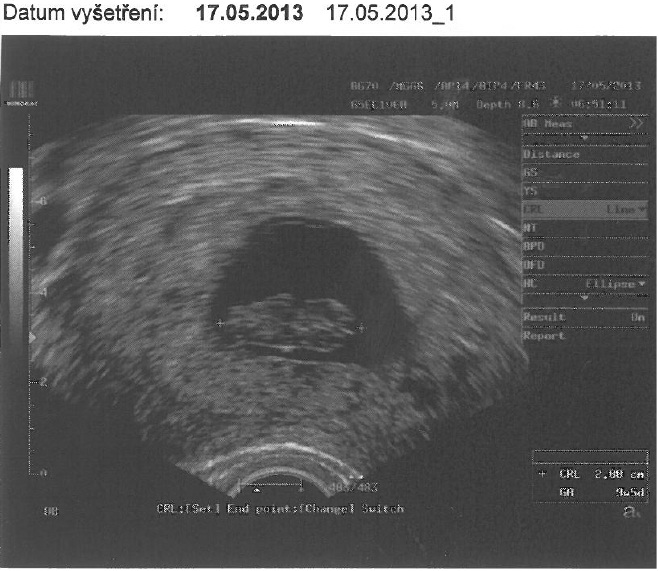

Tak dnes jsem byla na odběrech krve na screening a pan doktor mi uděl i ultrazvuk, aby věděl jak je mrňousek veliký, aby nás pak včas objednali na samotný screening. Na ten jdeme teda 5.6.

. Dnes odpovídáme 11+2, takže drobeček začíná dohánět tu týdenní ztrátu ze začátku. Bylo to ale naprosto úžadný, nejkrásnějších 4,47 cm které jsem zatím viděla. Mrňousek měl asi zrovna diskotéku, mlel sebou jako o život

Tak tady je slibovaný obrázek. Teď už budeme určitě o kus větší. Nevolnosti ustupují, naposledy jsem zvracela v neděli, ale nerada bych to zakřikla. K večeru to bývá ještě docela síla, ale je to o dost lepší.